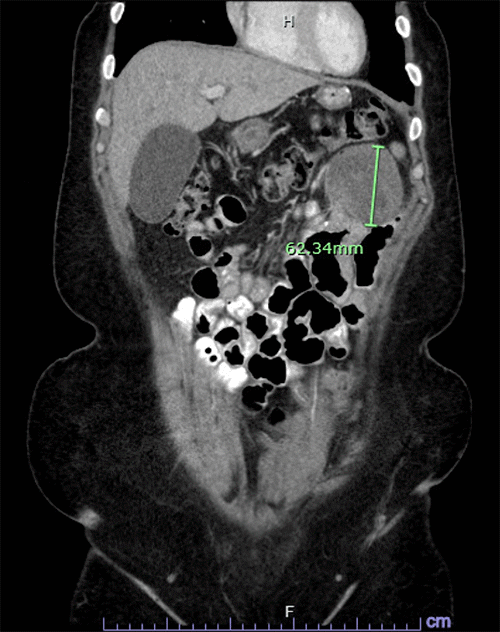

A 41-year-old woman presents with a triad of mild diffuse abdominal pain, nausea, and malaise. Abdominal CT scan revealed a 6 cm cystic-solid heterogenous complex mass in the left upper quadrant (Figure 1). Her past medical history is significant for morbid obesity, currently controlled hypertension, and prediabetes status following Roux-en-Y gastric bypass (RYGB) two years prior. Surgical history includes left salpingectomy for ectopic pregnancy in 2006 and total laparoscopic hysterectomy for cervical intraepithelial neoplasia grade 2 (CIN-2), dysfunctional uterine bleeding, and severe dysmenorrhea in 2011. Family history is notable for breast cancer in her sister and trisomy 4 in her eldest son. Physical exam revealed only mild left upper quadrant abdominal tenderness.

Figure 1. CT Scan of Well-defined Heterogeneous Mass in Left Upper Quadrant. Published with Permission

Horizontal view (★tumor)

B) coronal view